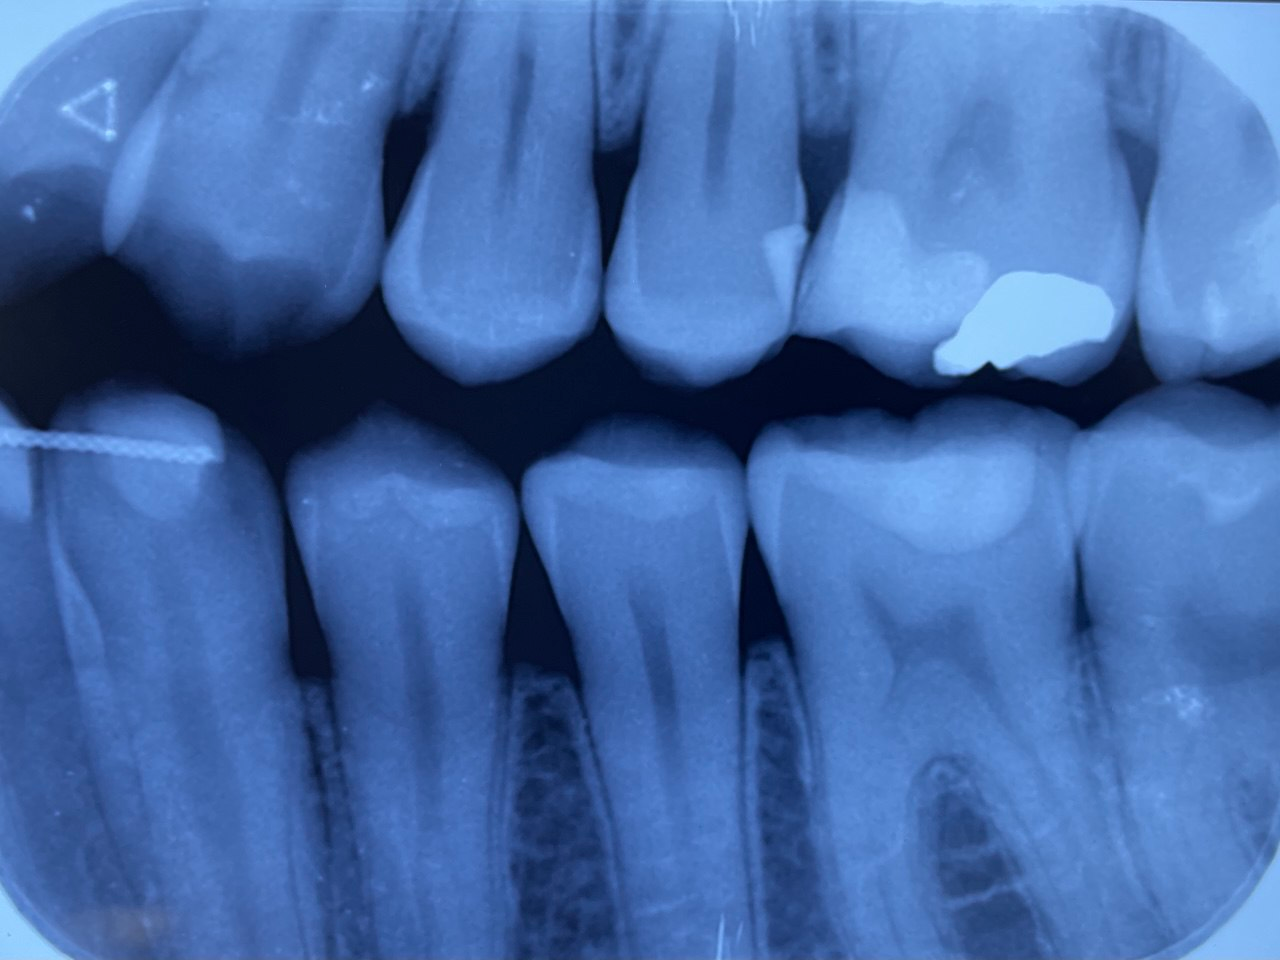

13. what are the radiolucency features in mesial and distal root surface of the tooth # 4.5 respectively?

14. Which surfaces shows recurrent caries?

15. Which surface shows recurrent caries?

22. What is the caries level of distal surface of tooth # 3.3?

23. What is the caries on distal surface of the tooth #2.4?

24. What are the caries level in distal surface th # 4.4, Mesial surface tooth # 4.5 respectively?

25. What are the caries level in distal surface of the tooth # 1.4, Mesial surface of the tooth # 1.5 respectively?